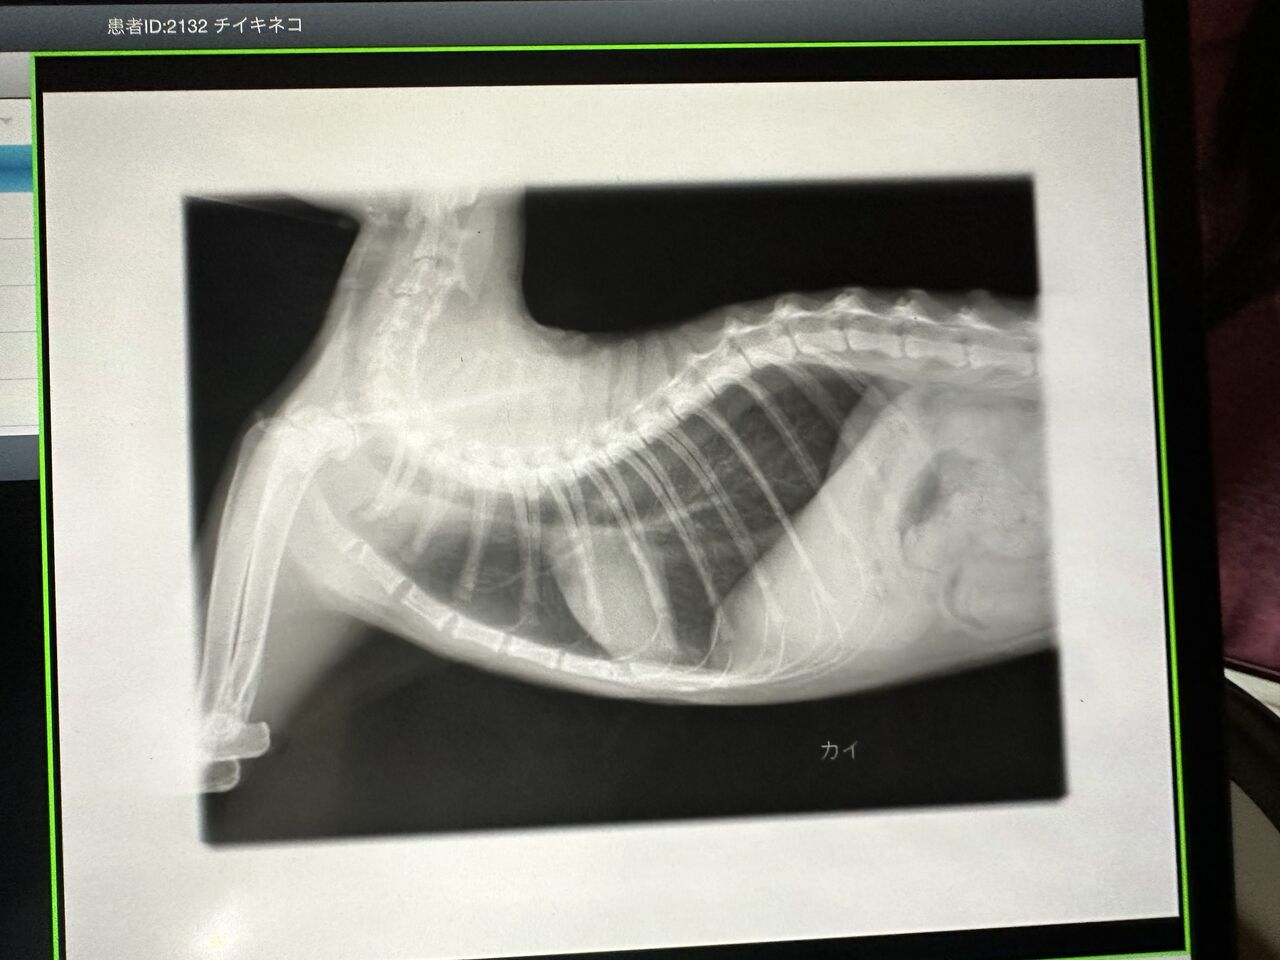

レントゲンも

相変わらず私が見てもあまりわかりませんが、

先生いわく問題なかったそうです